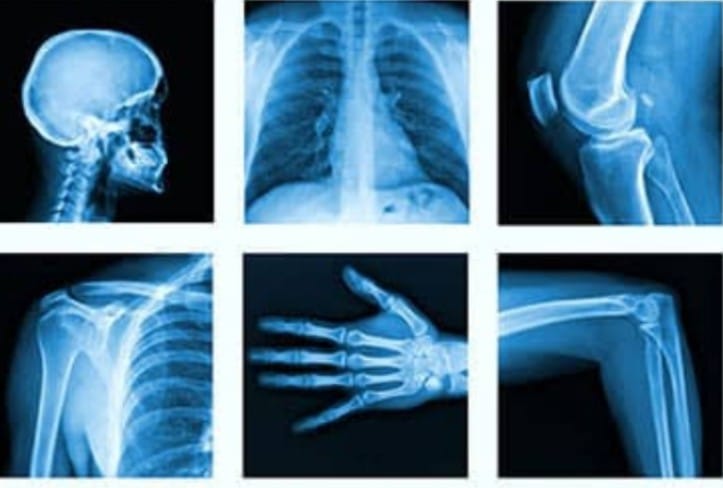

Transforming Lives: How X-Ray Services Can Make a Difference in Healthcare

For Priya, the RD Diagnostic Center & Wellness Clinic offered a lifeline. Their X-Ray services provided her with the clarity and assurance she desperately needed. This is not just a story about an X-Ray; it's about how timely and precise diagnostic services can transform lives.

At RD Diagnostic, the X-Ray services are designed with the patient in mind. Their state-of-the-art technology ensures fast and accurate results, allowing individuals like Priya to understand their health better and take informed steps towards recovery. The experienced radiologists at the clinic interpret the results with precision, offering insights that help demystify complex health issues.

For Priya, the X-Ray revealed a manageable condition that could be treated with physiotherapy and lifestyle adjustments. The relief she felt was immense. The fear of a severe, unidentified health issue had weighed heavily on her, and having a clear diagnosis allowed her to focus on her recovery without the burden of uncertainty. With a treatment plan in place, Priya was able to return to her classroom, her passion for teaching reignited and her quality of life restored.

Consider the case of Rajesh, a 45-year-old software engineer who, like Priya, found himself grappling with unexplained health issues. His job required long hours in front of a computer, leading to unexplained headaches and vision problems. A visit to RD Diagnostic and a subsequent X-Ray unveiled a neck alignment issue caused by poor posture. Armed with this knowledge, Rajesh was able to make necessary adjustments to his workstation and seek physiotherapy, ultimately alleviating his symptoms and improving his quality of life.

Through these stories, we see that the impact of X-Ray services extends beyond just the physical. They provide a sense of certainty in a world where health concerns can be daunting and overwhelming. For many, the ability to understand their condition and take proactive steps towards wellness is a game-changer.

In conclusion, the X-Ray services at RD Diagnostic Center & Wellness Clinic are more than just a medical examination. They are a gateway to better health, offering individuals the chance to reclaim their lives from the clutches of uncertainty and fear. For Priya, Rajesh, and countless others, these services have made a profound difference, proving that with the right support, we can all face our health challenges with courage and clarity.